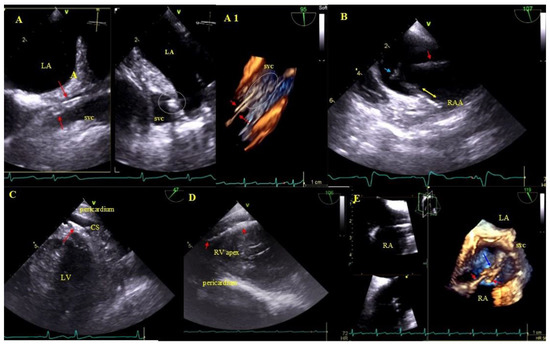

2.4. Preoperative TEE

2.5. Echocardiographic Findings Associated with Endocardial Leads: Definition and Classification According to the Anatomy and Characteristic Features